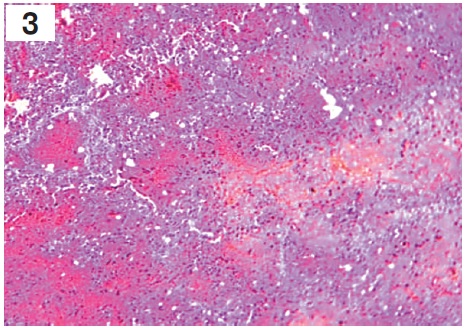

Рисунок 2. Микроскопическая картина микроабсцесса в легочной ткани: некротические очаги, сформировавшие микроабсцесс с пиогенной мембраной и лейкоцитарным валом по периферии. В окружении микроабсцесса определяются спавшиеся альвеолы с некротически измененными стенками. Окраска гематоксилином и эозином (×900) / Figure 2. Microscopic picture of necrotic foci with a pyogenic membrane and a leukocyte shaft on the periphery. Surrounded by a microabscess, collapsed alveoli with necrotically modified walls are detected. Stained with hematoxylin and eosin, ×900

В легких были выявлены признаки двусторонней тотальной геморрагической пневмонии. При макроскопическом исследовании: легкие с двух сторон плотной консистенции, тяжелые, безвоздушные, отечные, синюшного цвета. При гистологическом исследовании определялись неравномерно расправленные альвеолы с утолщенными межальвеолярными перегородками за счет отека и полнокровия, признаки пролиферации эндотелиоцитов капилляров, десквамация альвеолярного эпителия, отек, мононуклеарная инфильтрация, в альвеолах и альвеолярных ходах наблюдались гиалиновые мембраны. Также выявлялись участки некроза альвеолярного эпителия с обнажением базальной мембраны и признаками выраженного отека с геморрагическим компонентом, в просвете альвеол встречались гемолизированные эритроциты, гемосидерин, гемосидерофаги. Визуализировались очаговые кровоизлияния в легочной паренхиме, местами сливающиеся, с выходом форменных элементов крови в просвет альвеол и участки некроза легочной ткани с формированием «гнойников» (микроабсцессов), в зонах некроза встречались микробные колонии. В окружности участка некроза отмечался хорошо выраженный вал из зернистых лейкоцитов. В альвеолах, расположенных ближе к гнойникам, определялся фибринозный и серозный экссудат (рис. 2 и 3, вклейка, с. II).